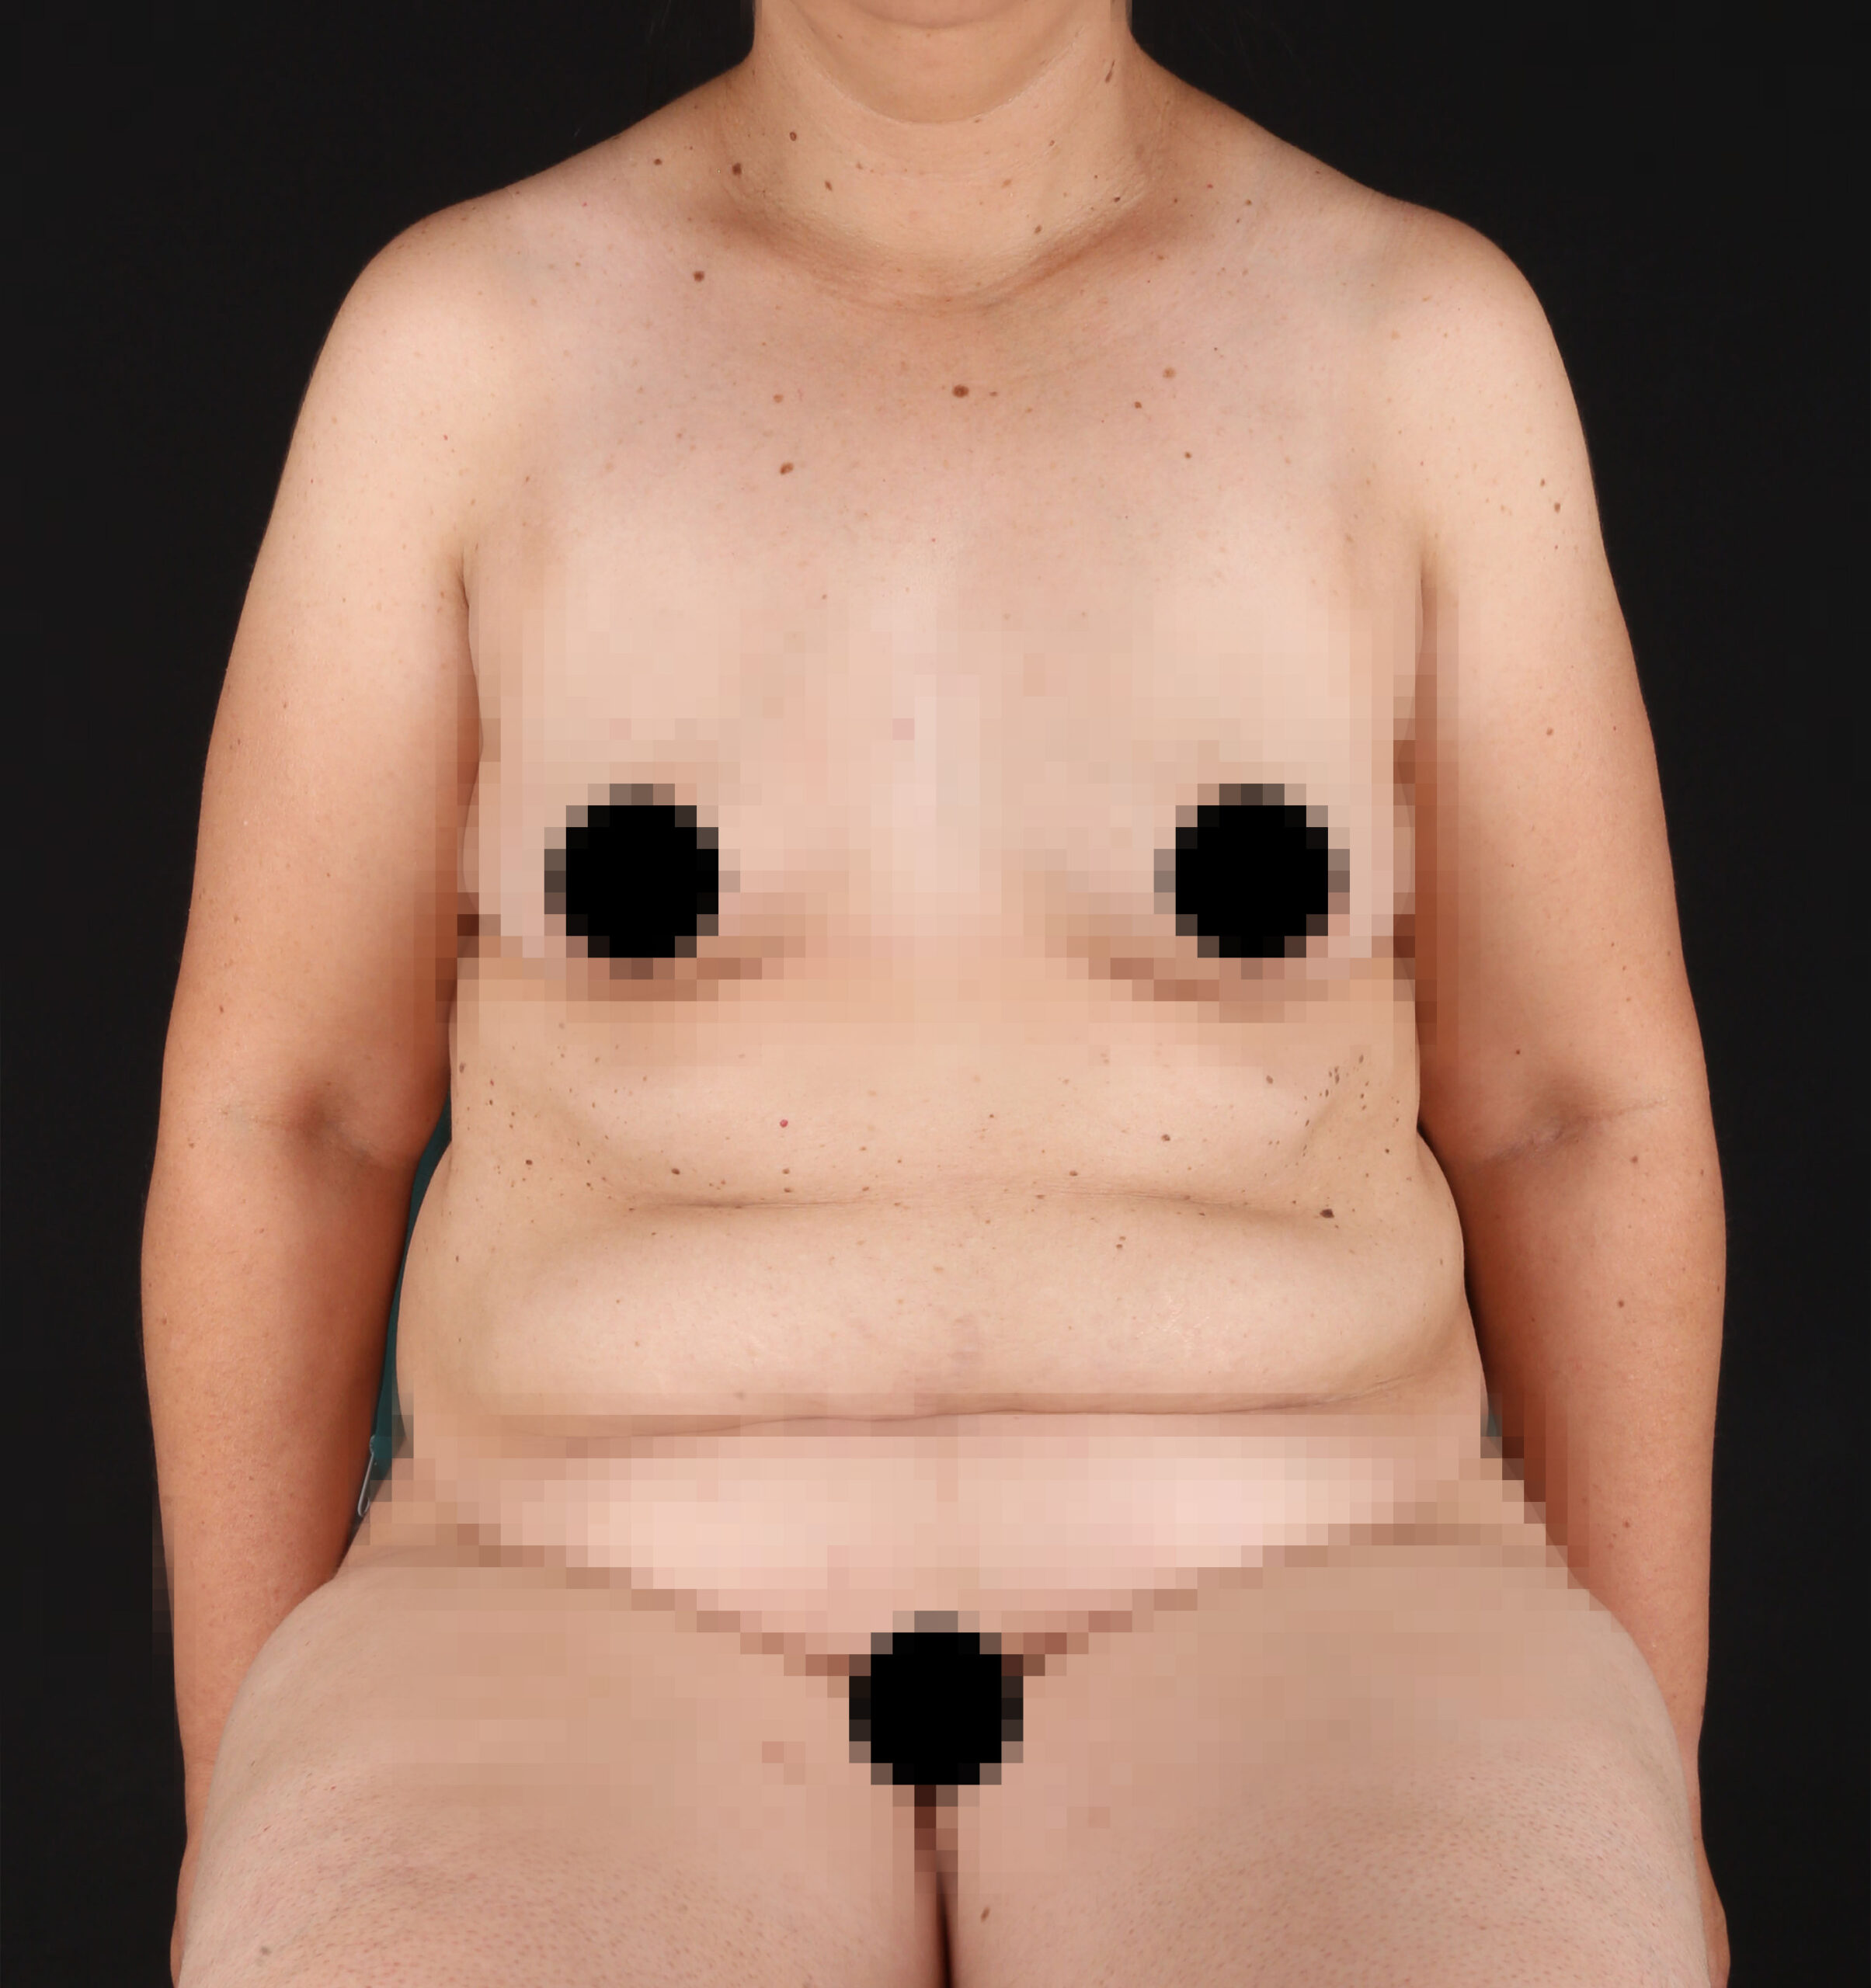

Es una ayuda diagnóstica complementaria que se utiliza para capturar imágenes de cualquier parte del cuerpo, aplicando técnicas que permitan obtener fotografías proporcionales, detalladas y nítidas; empleadas para medir, trazar, predeterminar y planear un proceso quirúrgico.

Es utilizada para crear imágenes del cuerpo humano, o partes de él, con propósitos clínicos que buscan revelar, diagnosticar y planear un tratamiento médico.